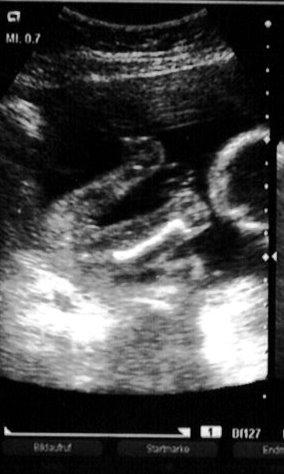

Juhu, waren heut mal beim US und der Zwerg hat sich nun so richtig schön von unten zeigen lassen an die die schon ein Outing haben, was könnt ihr da erkennen? lg Krissel

Bild zu Ist das eindeutig??? - Forum für März - Mamis

Ich würde auf Mädchen tippen!!!!! ;-)

Ja das haben wir auch gleich vermutet aber sehen die Schamlippen schon so wulstig aus. Allerdings wäre der Hoden ja eher einer und rund, oder? Beim US war ich vollkommen überzeugt und nun bin ich schon wieder leicht verunsichert. Ok noch spätestens 18 Wochen wird sich das Geheimnis lüften

also ich würde nun auch auf nen mädel tippen, obwohl die sicht ja nicht sooo gut ist, aber beim jungen sieht man eindeutig die hoden, die ich jetzt hier vermisse, was sagt denn der doc zum geschlecht???